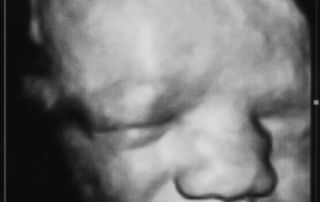

פרופ' ישראל מייזנר, הינו גינקולוג מבכירי הרופאים המומחים בארץ ובעולם בתחום האולטראסאונד, ובביצוע פעולות פולשניות תחת בקרת אולטראסאונד כגון בדיקות סיסי שליה ומי שפיר, דיקור ציסטות, עירוי דם לעובר ועוד.

לפרופ' מייזנר מרפאה פרטית בסביון בה הוא עורך לנשים בהריון בדיקות אולטרה סאונד הכוללות בדיקות שקיפות עורפית סקירות מערכות ויעוצים וחוות דעת למומים מולדים.